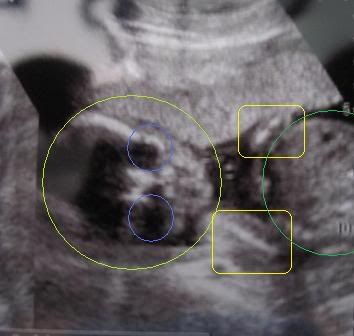

clearer view

haha heard feedback that so many of our friends cannot make out the picture that was posted on Hubby's blog.

so decided to use my crappy paint skills to make things a bit clearer. =P

the big lighter green circle : head

the 2 blue circles : eyes

the 2 yellow rectangles : arms

the big darker green circle : tummy

so can see her clearer now? lol =)